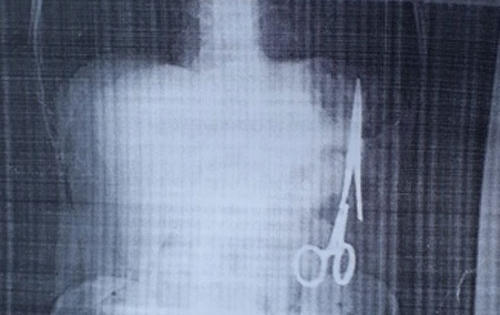

Bộ Y tế vào cuộc vụ "Kéo phẫu thuật bị bỏ quên 18 năm trong bụng bệnh nhân"

Ngay sau khi nhận được thông tin phản ánh về trường hợp của ông Ma Văn Nhật, 54 tuổi phát hiện trong ổ bụng có một chiếc kéo/panh dài 15 cm, Cục Quản lý Khám chữa bệnh đã có công văn gửi Sở Y tế Bắc Kạn yêu cầu làm rõ vụ việc trên.